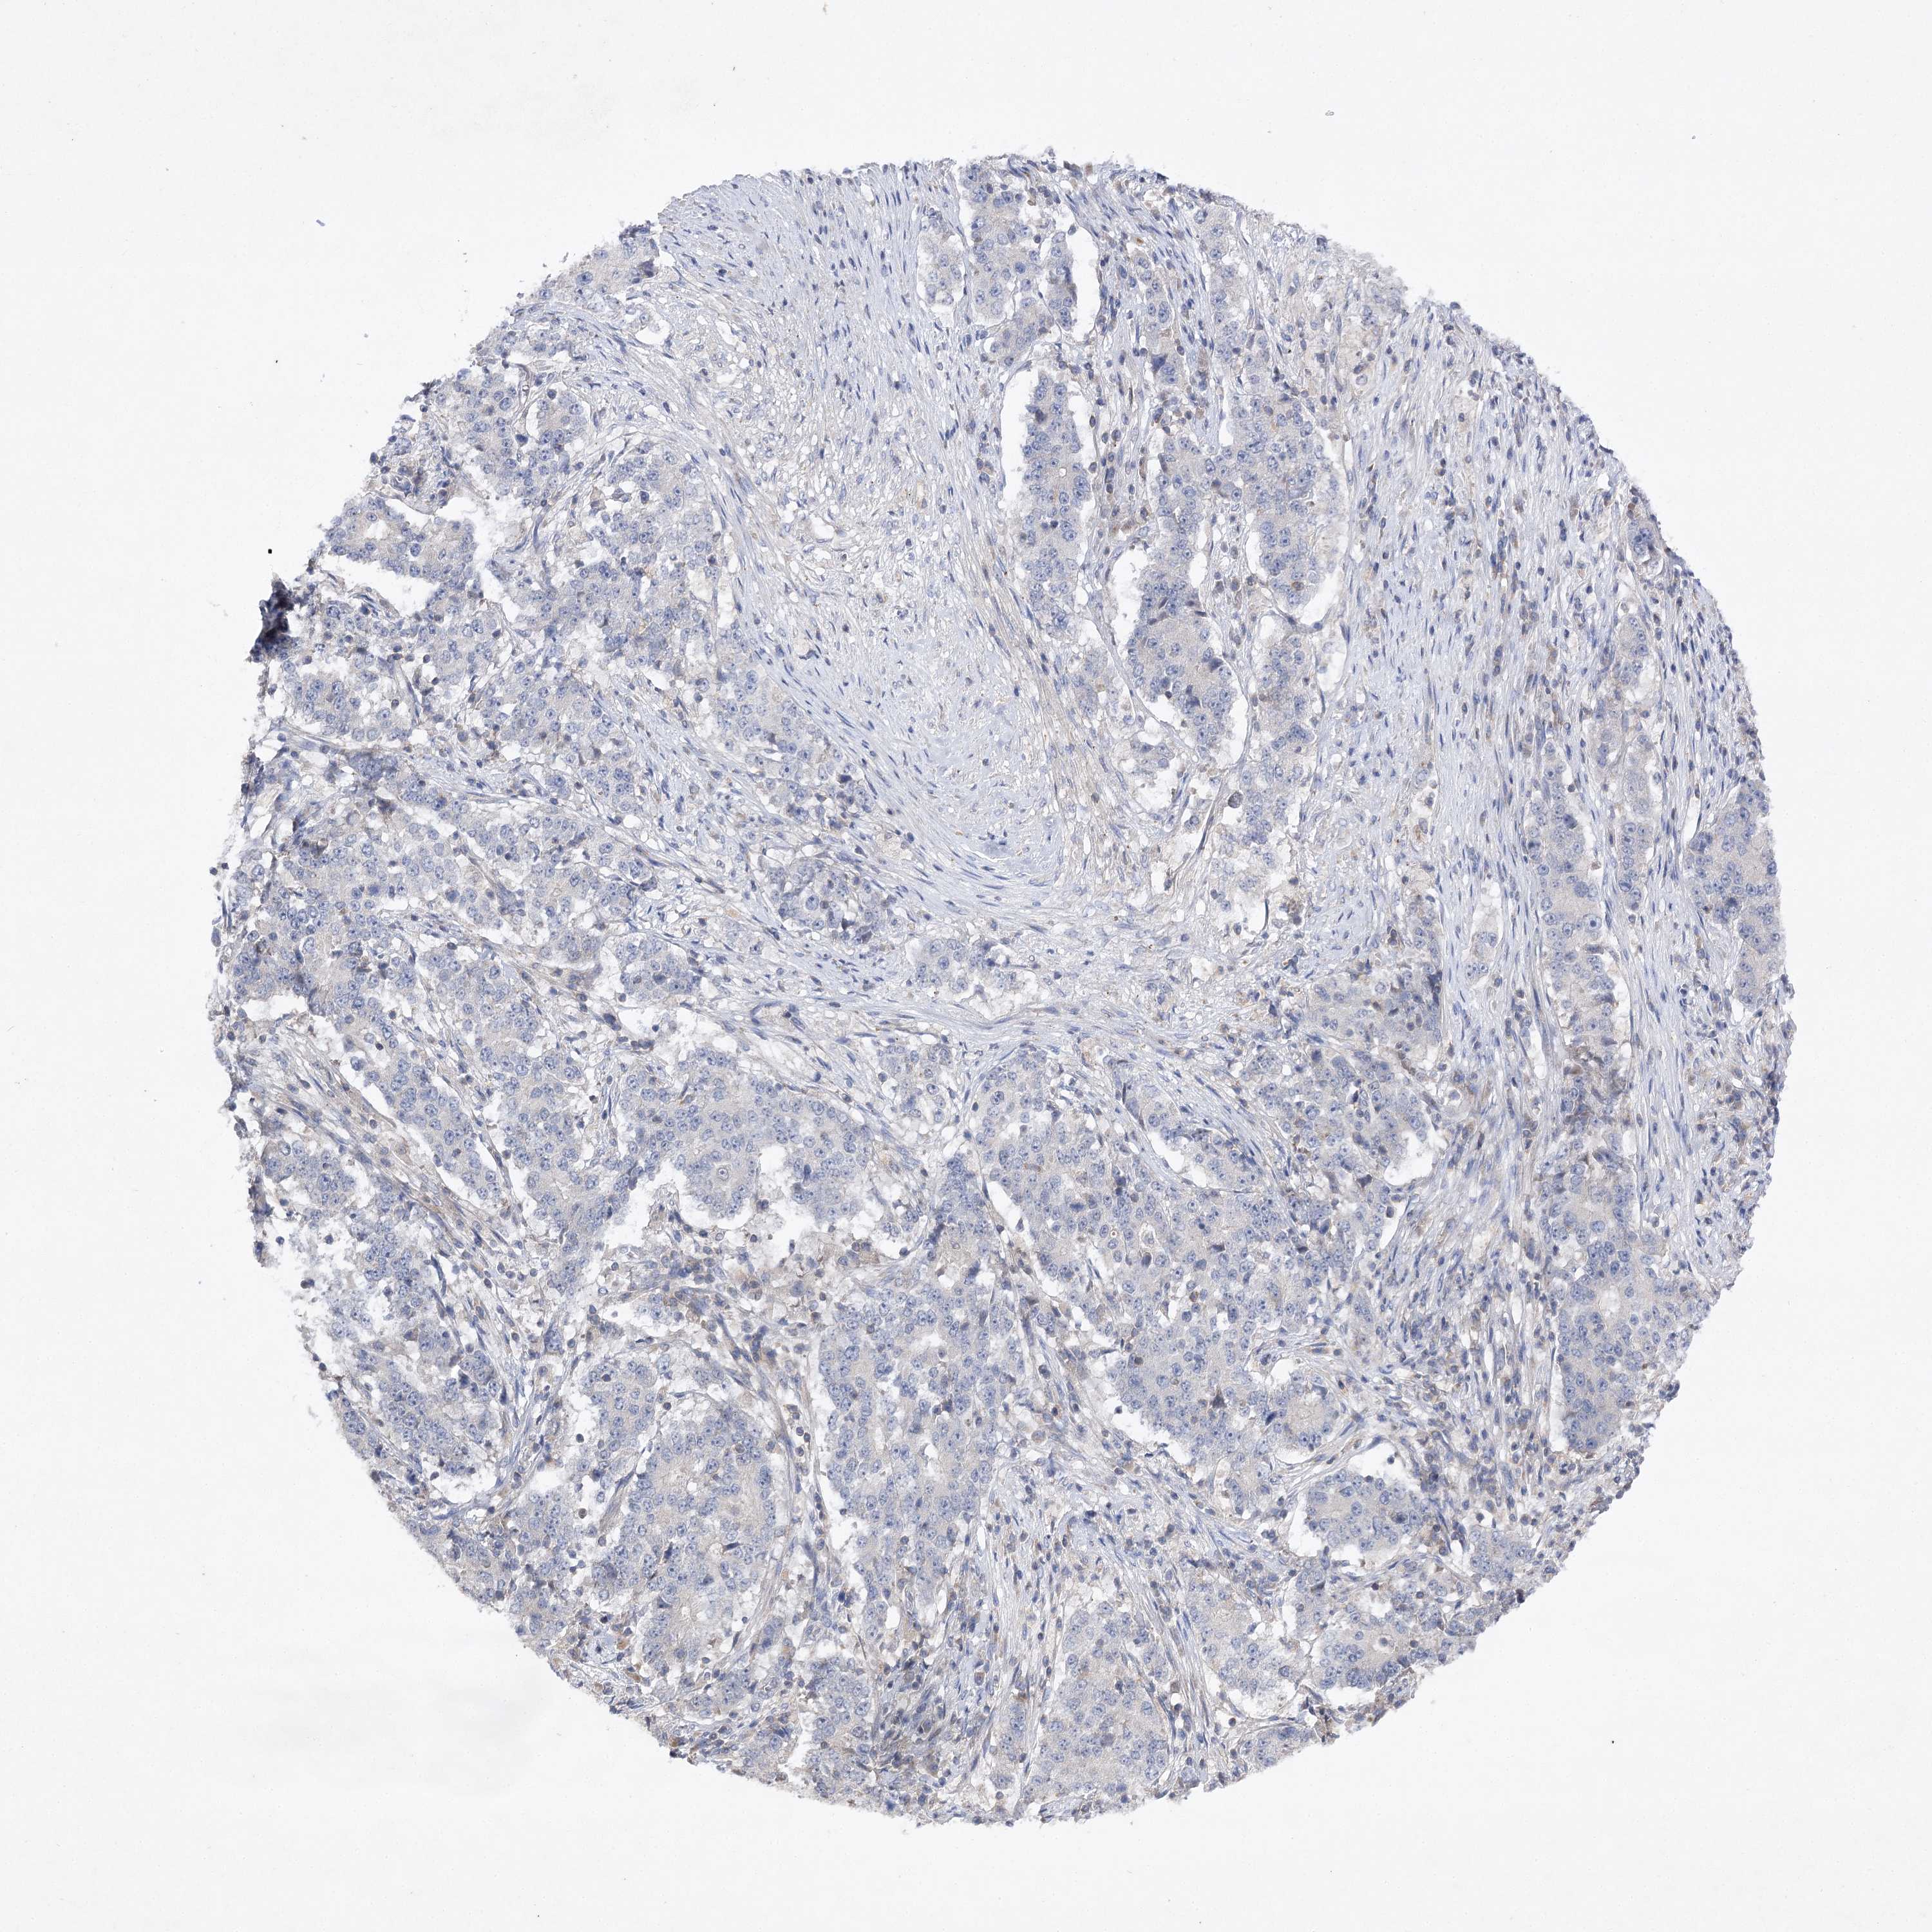

STOMACH CANCER - Protein expressioni

A mouse-over function shows sample information and annotation data. Click on an image to view it in a full screen mode. Samples can be filtered based on level of antibody staining by selecting one or several of the following categories: high, medium, low and not detected. The assay and annotation is described here.

Note that samples used for immunohistochemistry by the Human Protein Atlas do not correspond to samples in the TCGA dataset.

Antibody stainingi

Antibody staining in the annotated cell types in the current human tissue is reported as not detected, low, medium, or high, based on conventional immunohistochemistry profiling in selected tissues. This score is based on the combination of the staining intensity and fraction of stained cells.

Each image is clickable and will lead to virtual microscopy that enables deeper exploration of all samples and also displays staining intensity scores, fraction scores and subcellular localization as well as patient and tissue information for each sample.

Antibody HPA038337

Antibody CAB010421

Antibody CAB018545

Staining

Adenocarcinoma, NOS